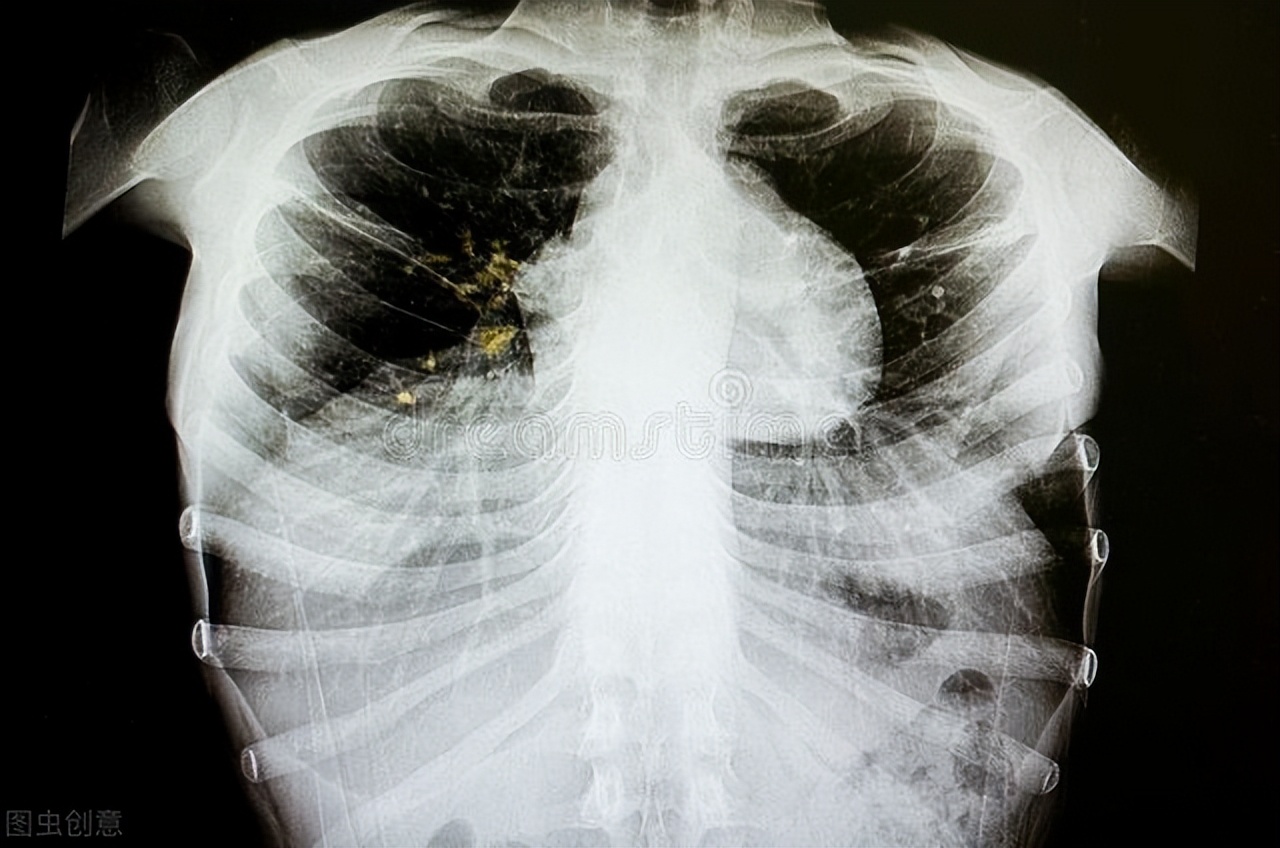

肺结核治疗的新方向!肠道微生物普雷沃菌与肺结核之间相关性研究

肺结核是一种严重危害人类健康的全球重大传染性疾病。研究表明,感染结核分枝杆菌后会出现肠道微生态的失衡,反之肠道菌群失调也会增加结核分枝杆菌的易感性。而普雷沃菌属是新发现的一种与炎症疾病紧密相关的肠道微生物,且在结核患者体内有明显的丰度变化。